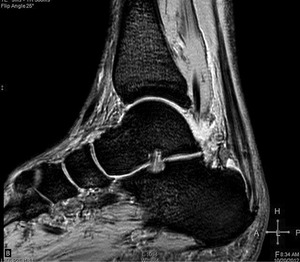

Pacjent, lat 52, zgłosił się do lekarza ortopedy z powodu silnego bólu w okolicy prawej pięty, który wystąpił nagle poprzedniego dnia podczas treningu piłki nożnej. Pacjent uprawia sport regularnie. Do tej pory nie cierpiał z powodu żadnych dolegliwości bólowych tej okolicy, a początek bólu nie był związany z bezpośrednim urazem. Podczas badania stopy okolica ścięgna Achillesa (piętowego) była obrzęknięta i bolesna, ruchy czynne w stawie skokowym znacznie ograniczone. Stwierdzono brak palpacyjnej bolesności w okolicy kostki przyśrodkowej i bocznej z zachowaną stabilnością w ruchach na boki.

Obrzęknięta okolica ścięgna Achillesa wraz z nagłym początkiem dolegliwości wskazuje na jego zerwanie. Niemniej możliwość wykonywania czynnych ruchów w stawie skokowym, nawet w niewielkim zakresie, przemawia za innym rozpoznaniem. Nie występuje też wyczuwalna luka w ścięgnie, jednak może być ona maskowana obrzękiem tej okolicy. Zapalenie kaletki głębokiej ścięgna Achillesa również może wywołać podobne objawy. Często wiąże się ono z występowaniem wyrośli kostnej na kości piętowej (deformacja Haglunda), która drażniąc kaletkę, wywołuje jej stan zapalny. Do złamań zmęczeniowych kości piętowej najczęściej dochodzi u żołnierzy oraz sportowców, którzy biegają długie dystanse po twardym podłożu. Jednakże w tym wypadku jest to mało prawdopodobne rozpoznanie, ponieważ pacjent może stanąć na pięcie oraz nie ma krwiaka i obrzęku tej okolicy.